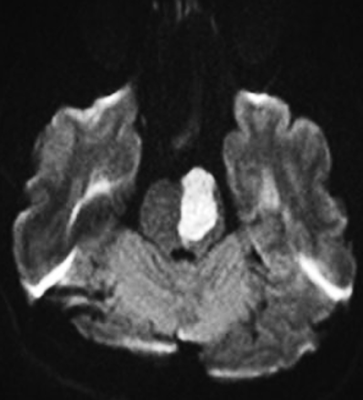

1. A 50-year-old woman with a known history of hypertension presented with an acute pontine hemorrhage, as demonstrated on computed tomography (arrow).

5. T2-weighted magnetic resonance imaging (MRI) of the brain demonstrated hyperintensity and hypertrophy of the inferior olivary nuclei.